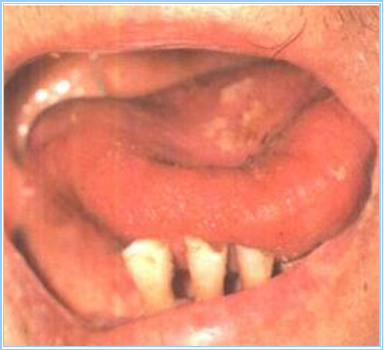

是位于舌系带两侧纵行的大络脉。

望舌下络脉主要观察其长度、形态、色泽、粗细、舌下小络脉等变化。其方法是:让病人张口,将舌体向上腭方向翘起,舌尖轻抵上腭,勿用力太过,使舌体自然放松,舌下络脉充分显露。首先观察舌系带两侧大络脉的长短、粗细、颜色、有无怒张、弯曲等异常改变,然后观察周围细小络脉的颜色、形态有无异常。

| 舌下络脉细而短,色淡红,周围小络脉不明显,舌色和舌下粘膜色偏淡 | 气血不足 |

| 舌下络脉粗胀 | 血瘀征象 |

| 舌下络脉呈青紫、紫红、绛紫、紫黑色 |

| 舌下细小络脉呈暗红色或紫色网状 |

| 舌下络脉曲张如紫色珠子状大小不等的瘀血结节 |